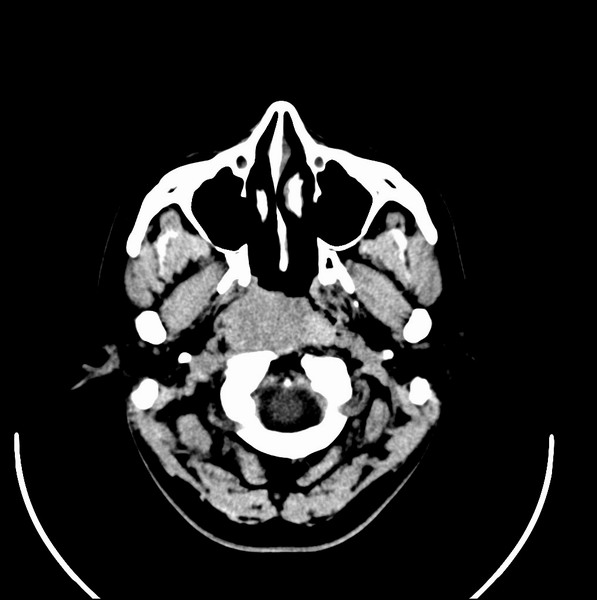

男、30、发现鼻咽部肿瘤侵犯海绵窦,未发现明显淋巴肿。请问国内那家医院治疗鼻咽部肿瘤最好?手术以何种方式为主?病灶可否全部切除?急切期待的大家的帮助。

扫描示鼻咽腔不对称,中度狭窄,右侧咽隐窝消失,局部软组织肿块,鼻咽右侧壁增厚形成肿块,突入鼻咽腔,肿块平扫呈等密度,肿块向深部侵润,右侧翼内外肌受侵,右侧咽旁间隙变窄;向后生长,头长肌界线欠清,向后上生长侵犯同侧颈动脉鞘区。双侧海绵窦增宽,内见软组织影与鼻咽部肿块相连。考虑鼻咽癌。鼻咽癌主要是放射治疗,且效果较好;到当地有治疗设备较大医院治疗即可。